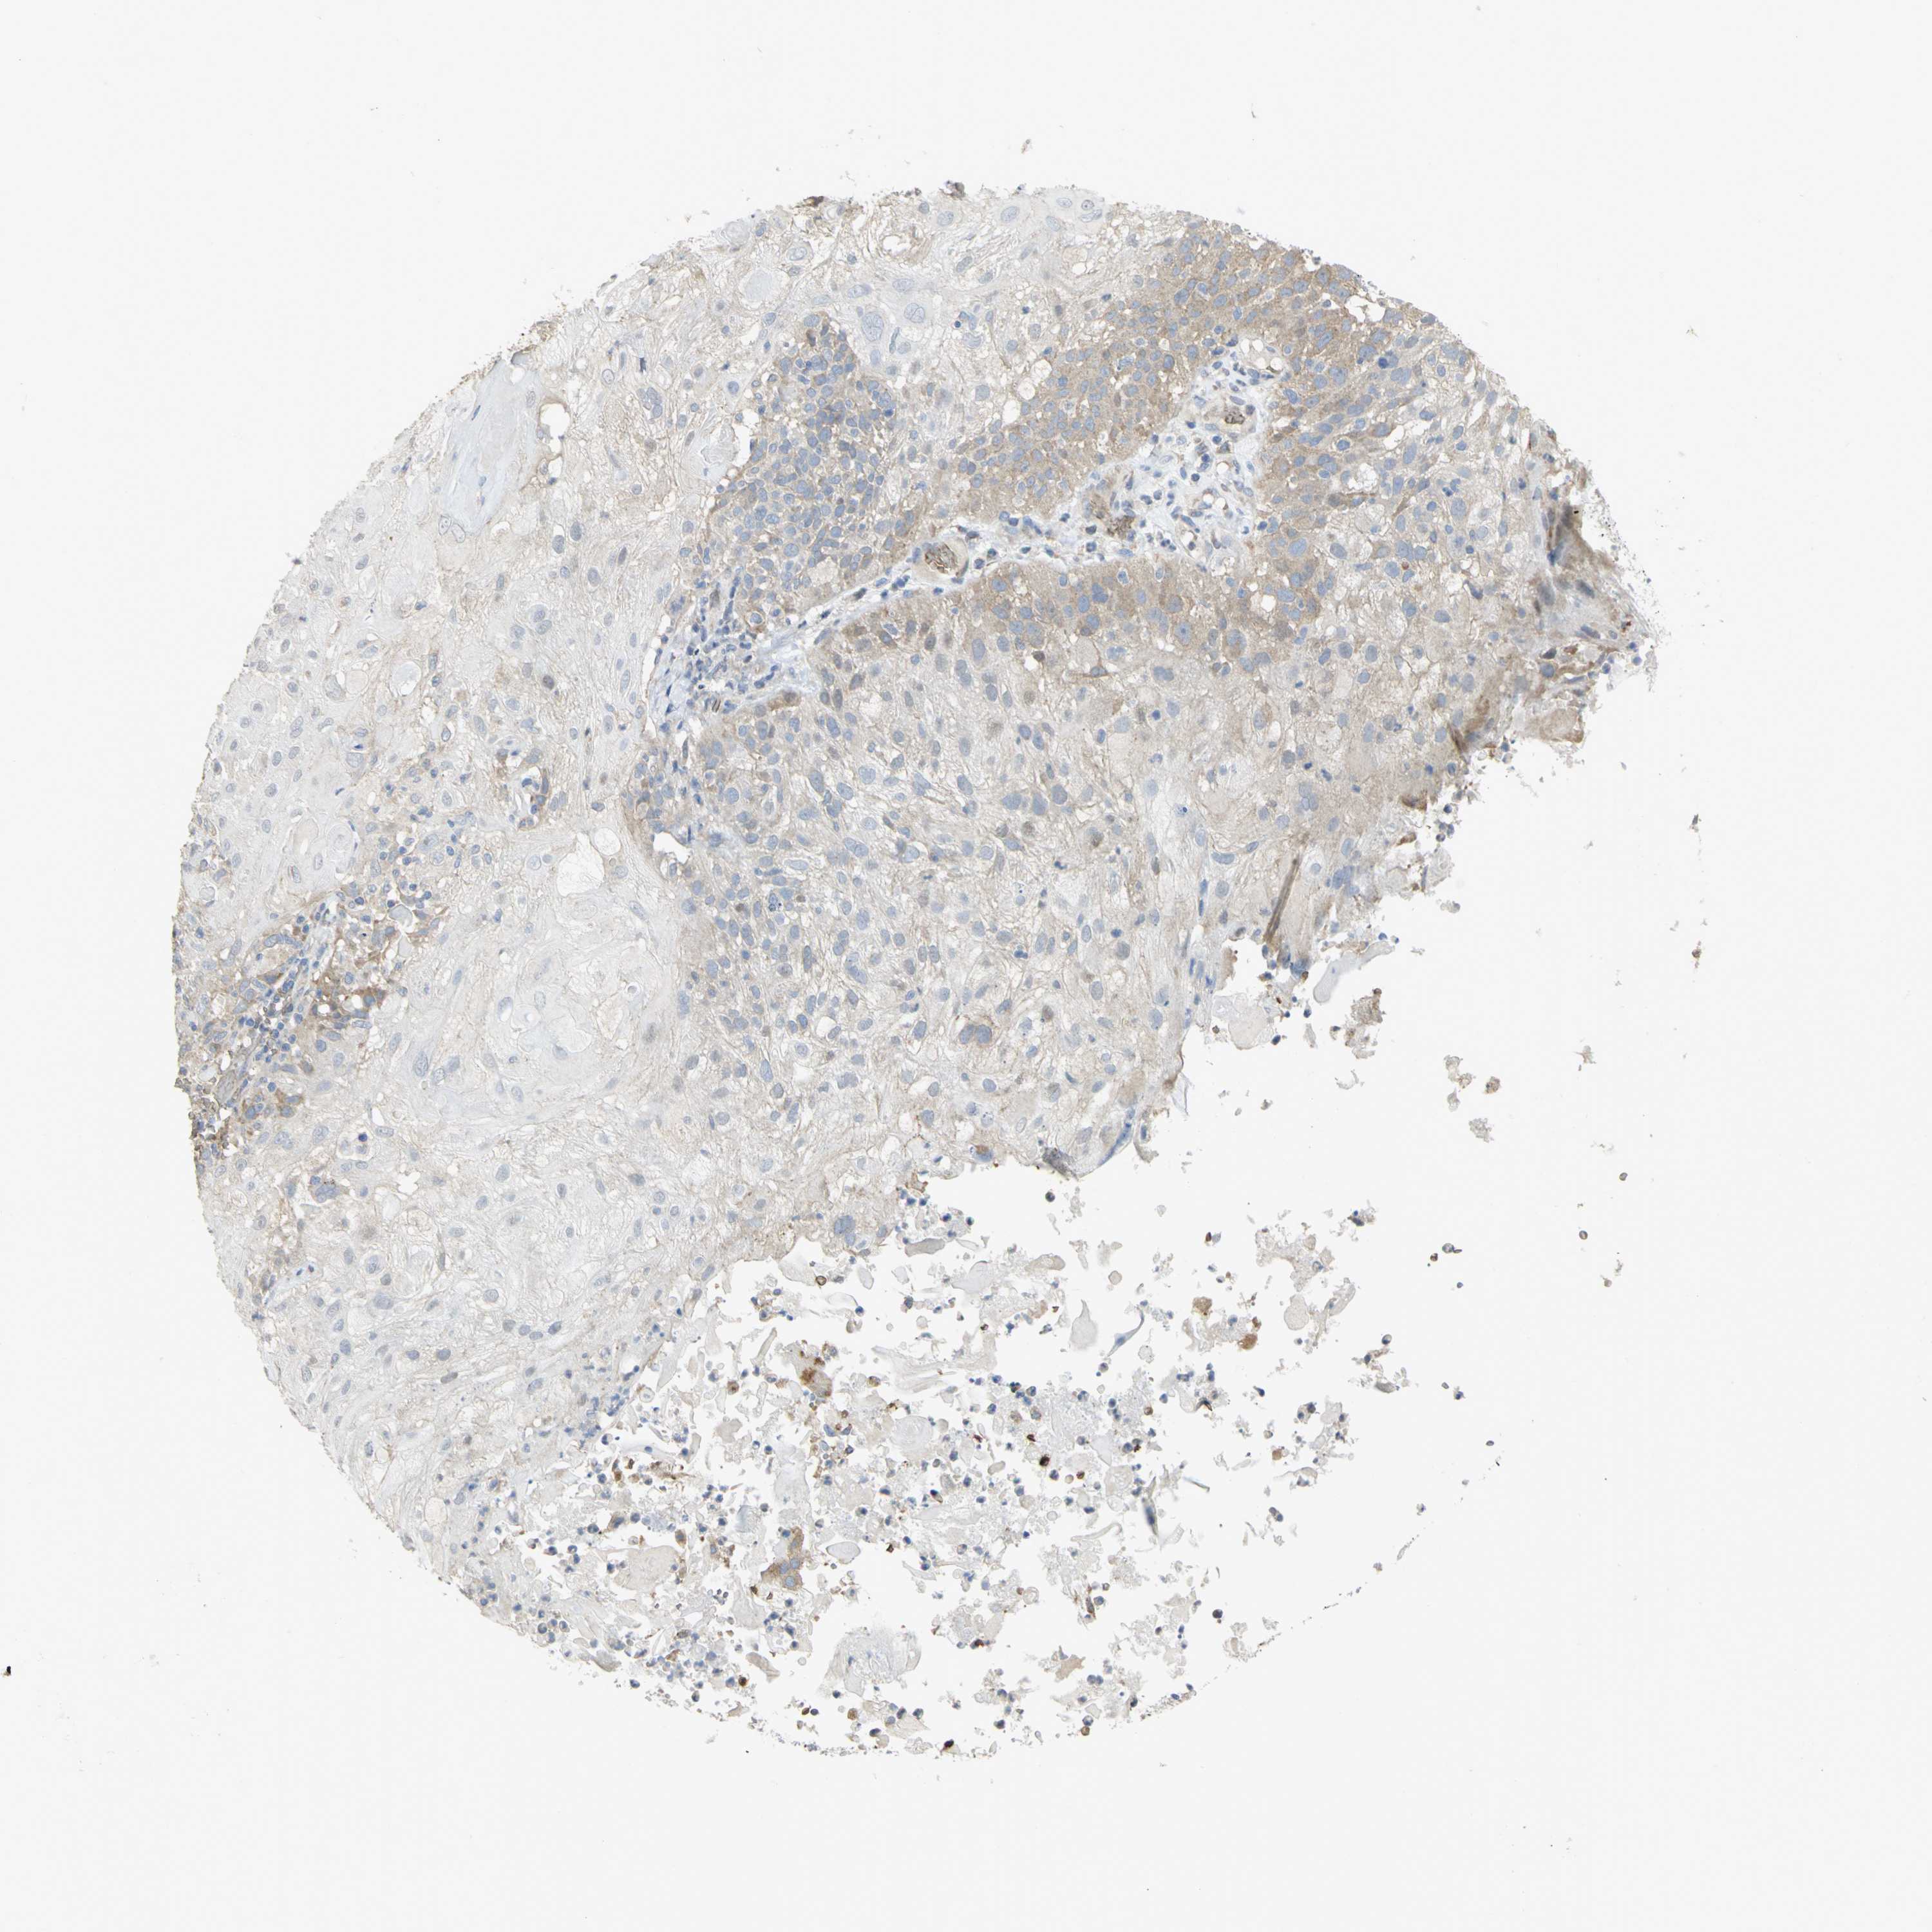

SKIN CANCER - Protein expressioni

A mouse-over function shows sample information and annotation data. Click on an image to view it in a full screen mode. Samples can be filtered based on level of antibody staining by selecting one or several of the following categories: high, medium, low and not detected. The assay and annotation is described here.

Antibody stainingi

Antibody staining in the annotated cell types in the current human tissue is reported as not detected, low, medium, or high, based on conventional immunohistochemistry profiling in selected tissues. This score is based on the combination of the staining intensity and fraction of stained cells.

Each image is clickable and will lead to virtual microscopy that enables deeper exploration of all samples and also displays staining intensity scores, fraction scores and subcellular localization as well as patient and tissue information for each sample.

Antibody HPA004842

Antibody HPA056953

Staining

High

Medium

Low

Not detected

Intensity

Strong

Moderate

Weak

Negative

Quantity

>75%

75%-25%

<25%

None

Location

Nuclear

Cytoplasmic/membranous

Cytoplasmic/membranous,nuclear

Squamous cell carcinoma, NOS

Basal cell carcinoma